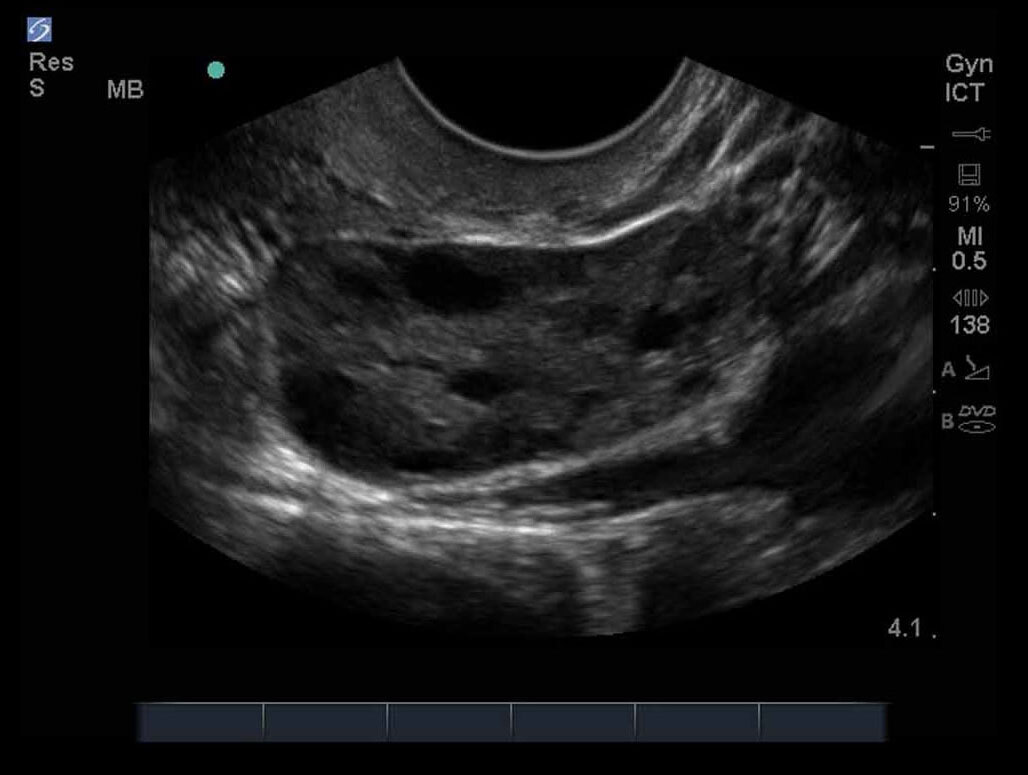

女性の骨盤09画像

M-Turbo:ICT 卵巣3。